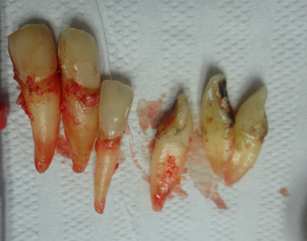

O final de uma periodontia inflamatória não tratada é este. A perda total dos dentes, todos íntegros, sem nenhuma cárie. Contudo, o biofilme por anos presente em suas superfícies, o tornaram para o Sistema Imunológico do paciente, um corpo extranho, ou seja um Antígeno.

Este (Ag), despertou todo o sistema imunológico do paciente, que iniciou a produção de anticorpos específicos (Ig), estimulando os osteoclastos a destruírem o osso alveolar, e iliminar o dente. Não foi o dentista que extraío estes dentes, mas o mecanismo de defesa do paciente os eliminou. Pois eles se tornaram um corpo extranho, que nesssecitava de ser eliminado, pois eles representavam um foco grave de inflamação, para o organismo do paciente.